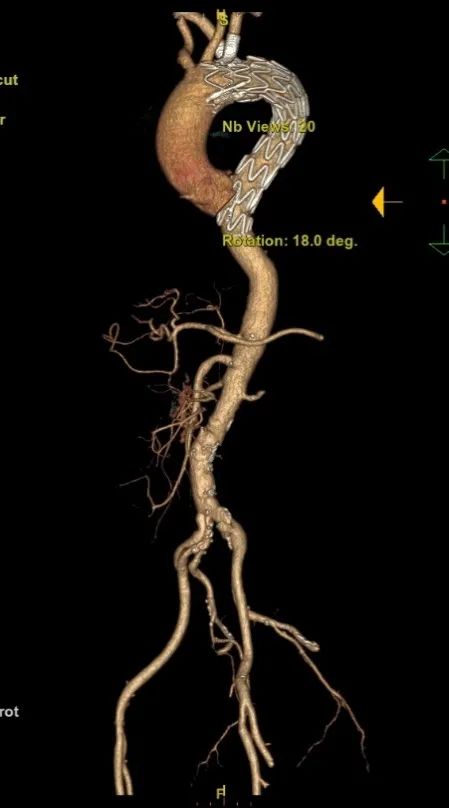

患者,男,56岁,腰背部疼痛4.5小时入院。

诊断:B型主动脉夹层、高血压、迷走右锁骨下动脉。

手术方案:TEVAR+迷走右锁骨下动脉烟囱+左锁骨下动脉烟囱或开窗(如果右侧烟囱不成功,可做右侧颈动脉-右锁骨下动脉人工血管搭桥)。

置入覆膜大支架;

右锁骨下动脉置入Viabahn和Smart Control支架(烟囱);

左侧置入Viabahn支架(烟囱);

术后造影复查,右侧迷走锁骨下动脉的烟囱支架角度平顺,血流通畅。

术后随访:

6个月后再次随访,CTA影像图显示血管形态良好,血管支架通畅。